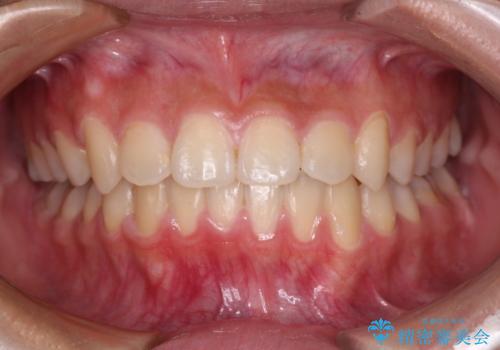

前歯のデコボコをインビザラインで綺麗に

- 上下前歯の叢生を気にして来院された患者様です。

インビザラインでの治療を希望されていて、デコボコの程度が中等度であり、安価なパッケージにて対応可能と判断されたため、インビザライン・モデレートを用いて矯正治療を行うこととしました。